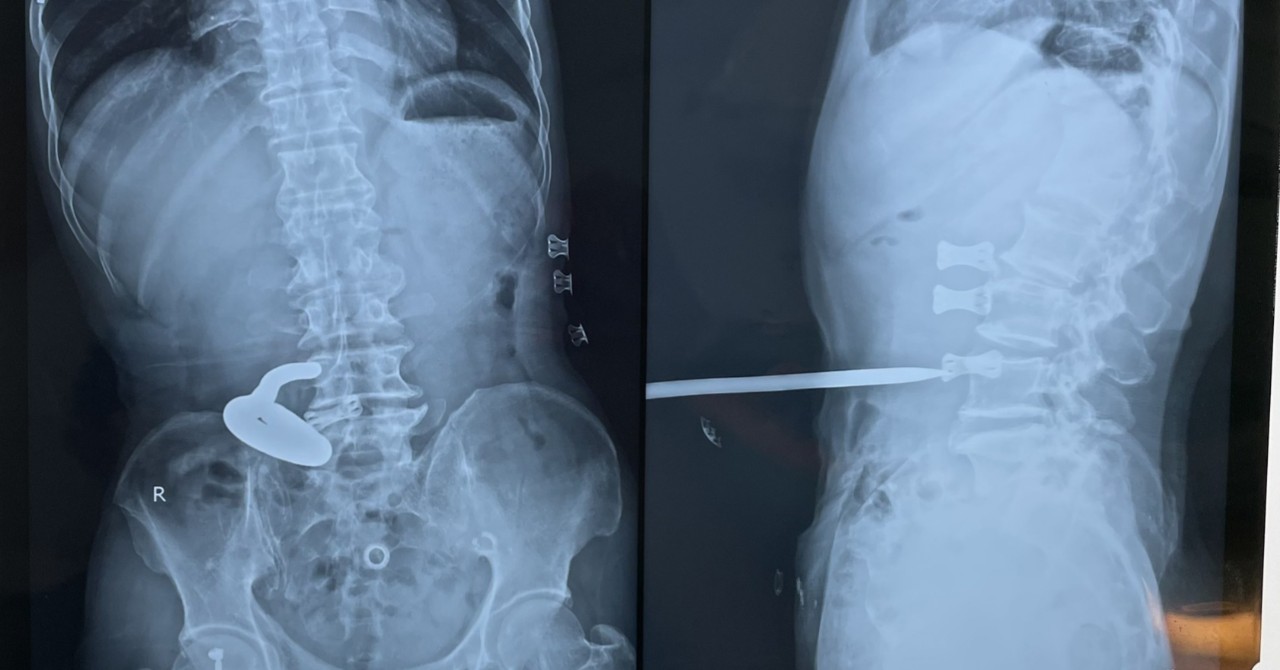

Vào lúc 15h34 phút, ngày 15/07/2024, khoa Ngoại tổng hợp- Bệnh viện ĐKKV Bắc Quảng Bình tiếp nhận người bệnh nam 52 tuổi, địa chỉ ở xã Quảng Phương, huyện Quảng Trạch vào viện trong tình trạng sốc chấn thương/ vết thương thấu bụng do cây sắt đâm, sond tiểu có máu đỏ tươi. Kíp trực đã tiến hành hồi sức tích cực, chụp X-Quang, siêu âm bụng, xét nghiệm tiền phẫu.

Dị vật là cây sắt kích thước 40cm x1cm

Dị vật là cây sắt kích thước 40cm x1cmCác Bác sỹ khoa ngoại đã tiến hành hội chẩn với khoa Gây mê- Hồi sức tiến hành phẫu thuật cấp cứu. Trong mổ, kiểm soát các tổn thương phát hiện dị vật đâm thủng thành sau phúc mạc, gây rách mạc treo đại tràng ngang, rách phúc mạc thành sau, gây vết thương tổn thương cực trên thận. Trong quá trình phẫu thuật đã lấy ra dị vật là cây sắt kích thước 40cm x1cm, khâu vết thương thận, cầm máu mạc treo.

Các Bác sỹ khoa ngoại đã tiến hành hội chẩn với khoa Gây mê - Hồi sức tiến hành phẫu thuật cấp cứu